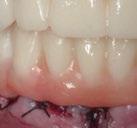

Figuras 4-8.

La exploración intraoral (figuras 4 a 8) revela una Clase II molar y canina completa, líneas 1/2 dentarias superior 0,5 mm e inferior 1 mm ambas desviadas hacia la derecha, los incisivos superiores excesivamente protruidos y vestibulizados (seguramente debido a la interposición del labio inferior), resalte de 13 mm y sobremordida 2/3 de corona. La discrepancia oseodentaria

inferior es de -3,5 mm y la curva de Spee de 4 mm.

En la ortopantomografía se aprecia una dentición permanente a falta de la erupción de los 2os y 3 os molares, así como una asimetría ósea con rama y cóndilo mandibular izquierdo menos desarrollado (figura 9), causante de la asimetría facial descrita anteriormente.

El estudio cefalométrico (figura 10) revela una Clase II esquelética por hipoplasia mandibular, patrón braquifacial e incisivos superiores muy protruidos (14,9 mm) y

vestibulizados (52º), e inferiores lingualizados (16 º). El perfil es extremadamente convexo.